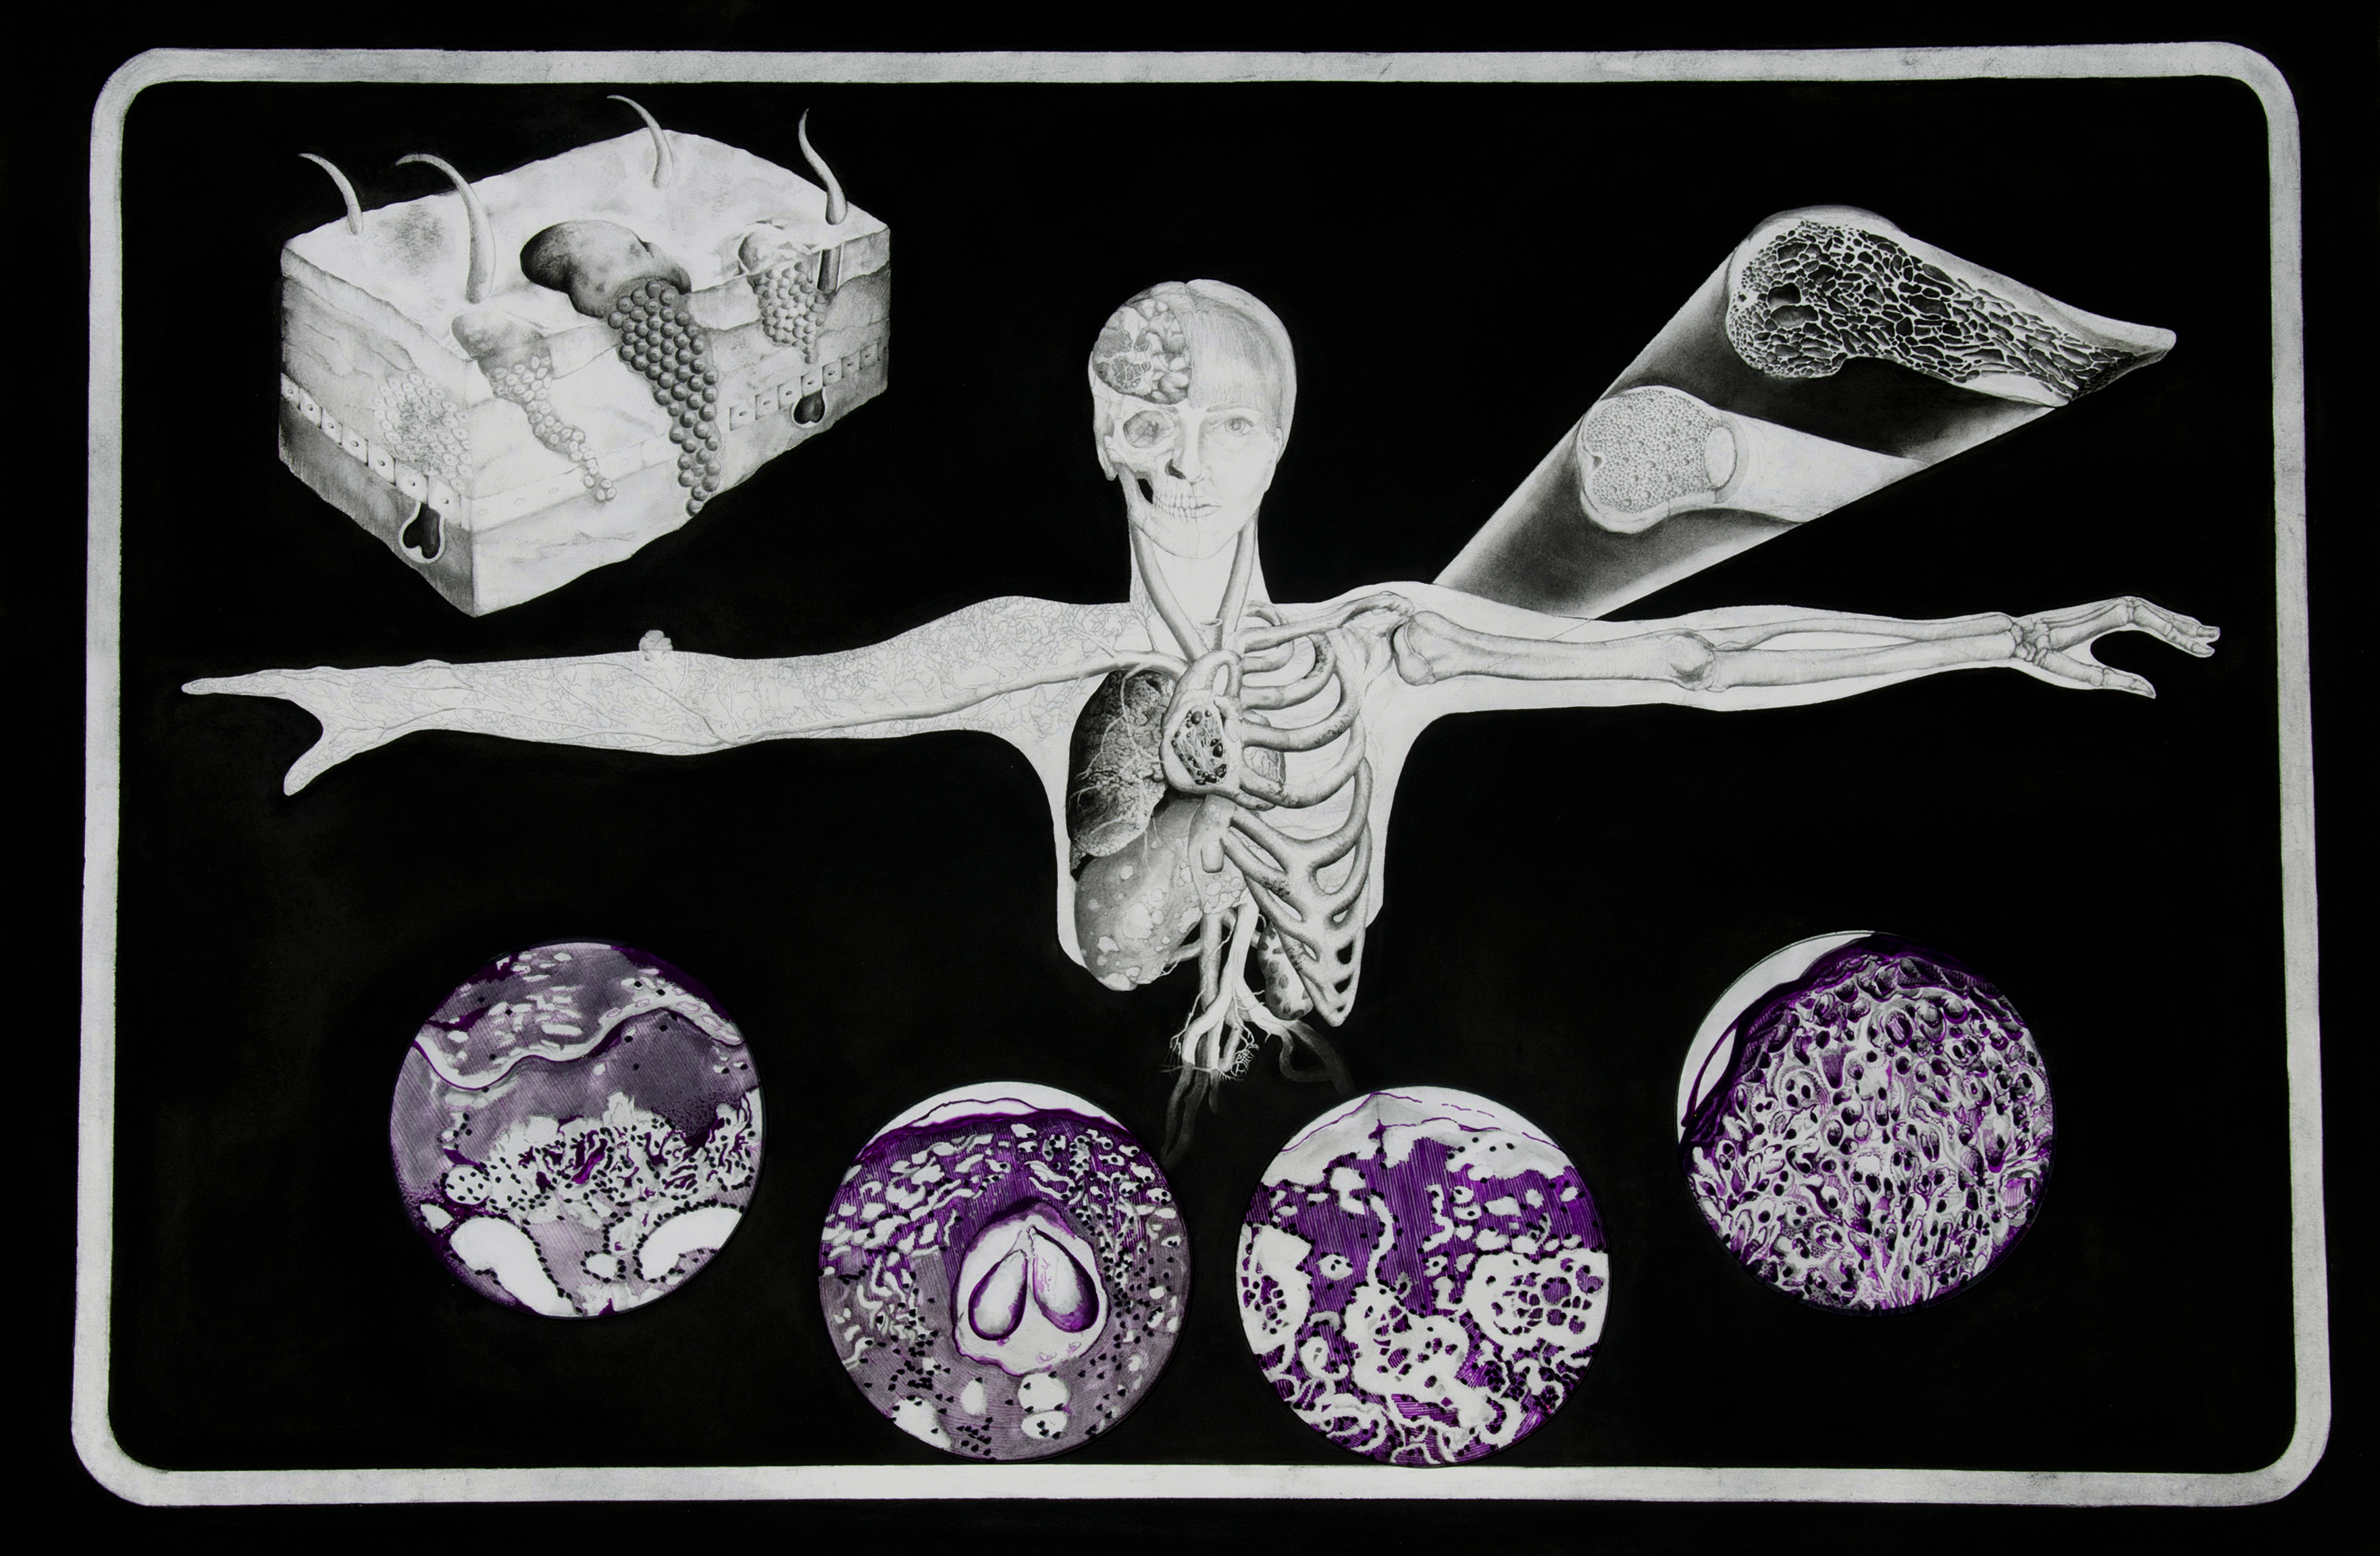

Visualizing Melanoma

Charcoal and graphite on paper with ink on Plexiglas and aluminum mounts

From Visual Pathology: a collaboration with Galveston Art Center and the Department of Pathology at the University of Texas Medical Branch (UTMB).

Image by Roxann Grover

Image by Roxann Grover